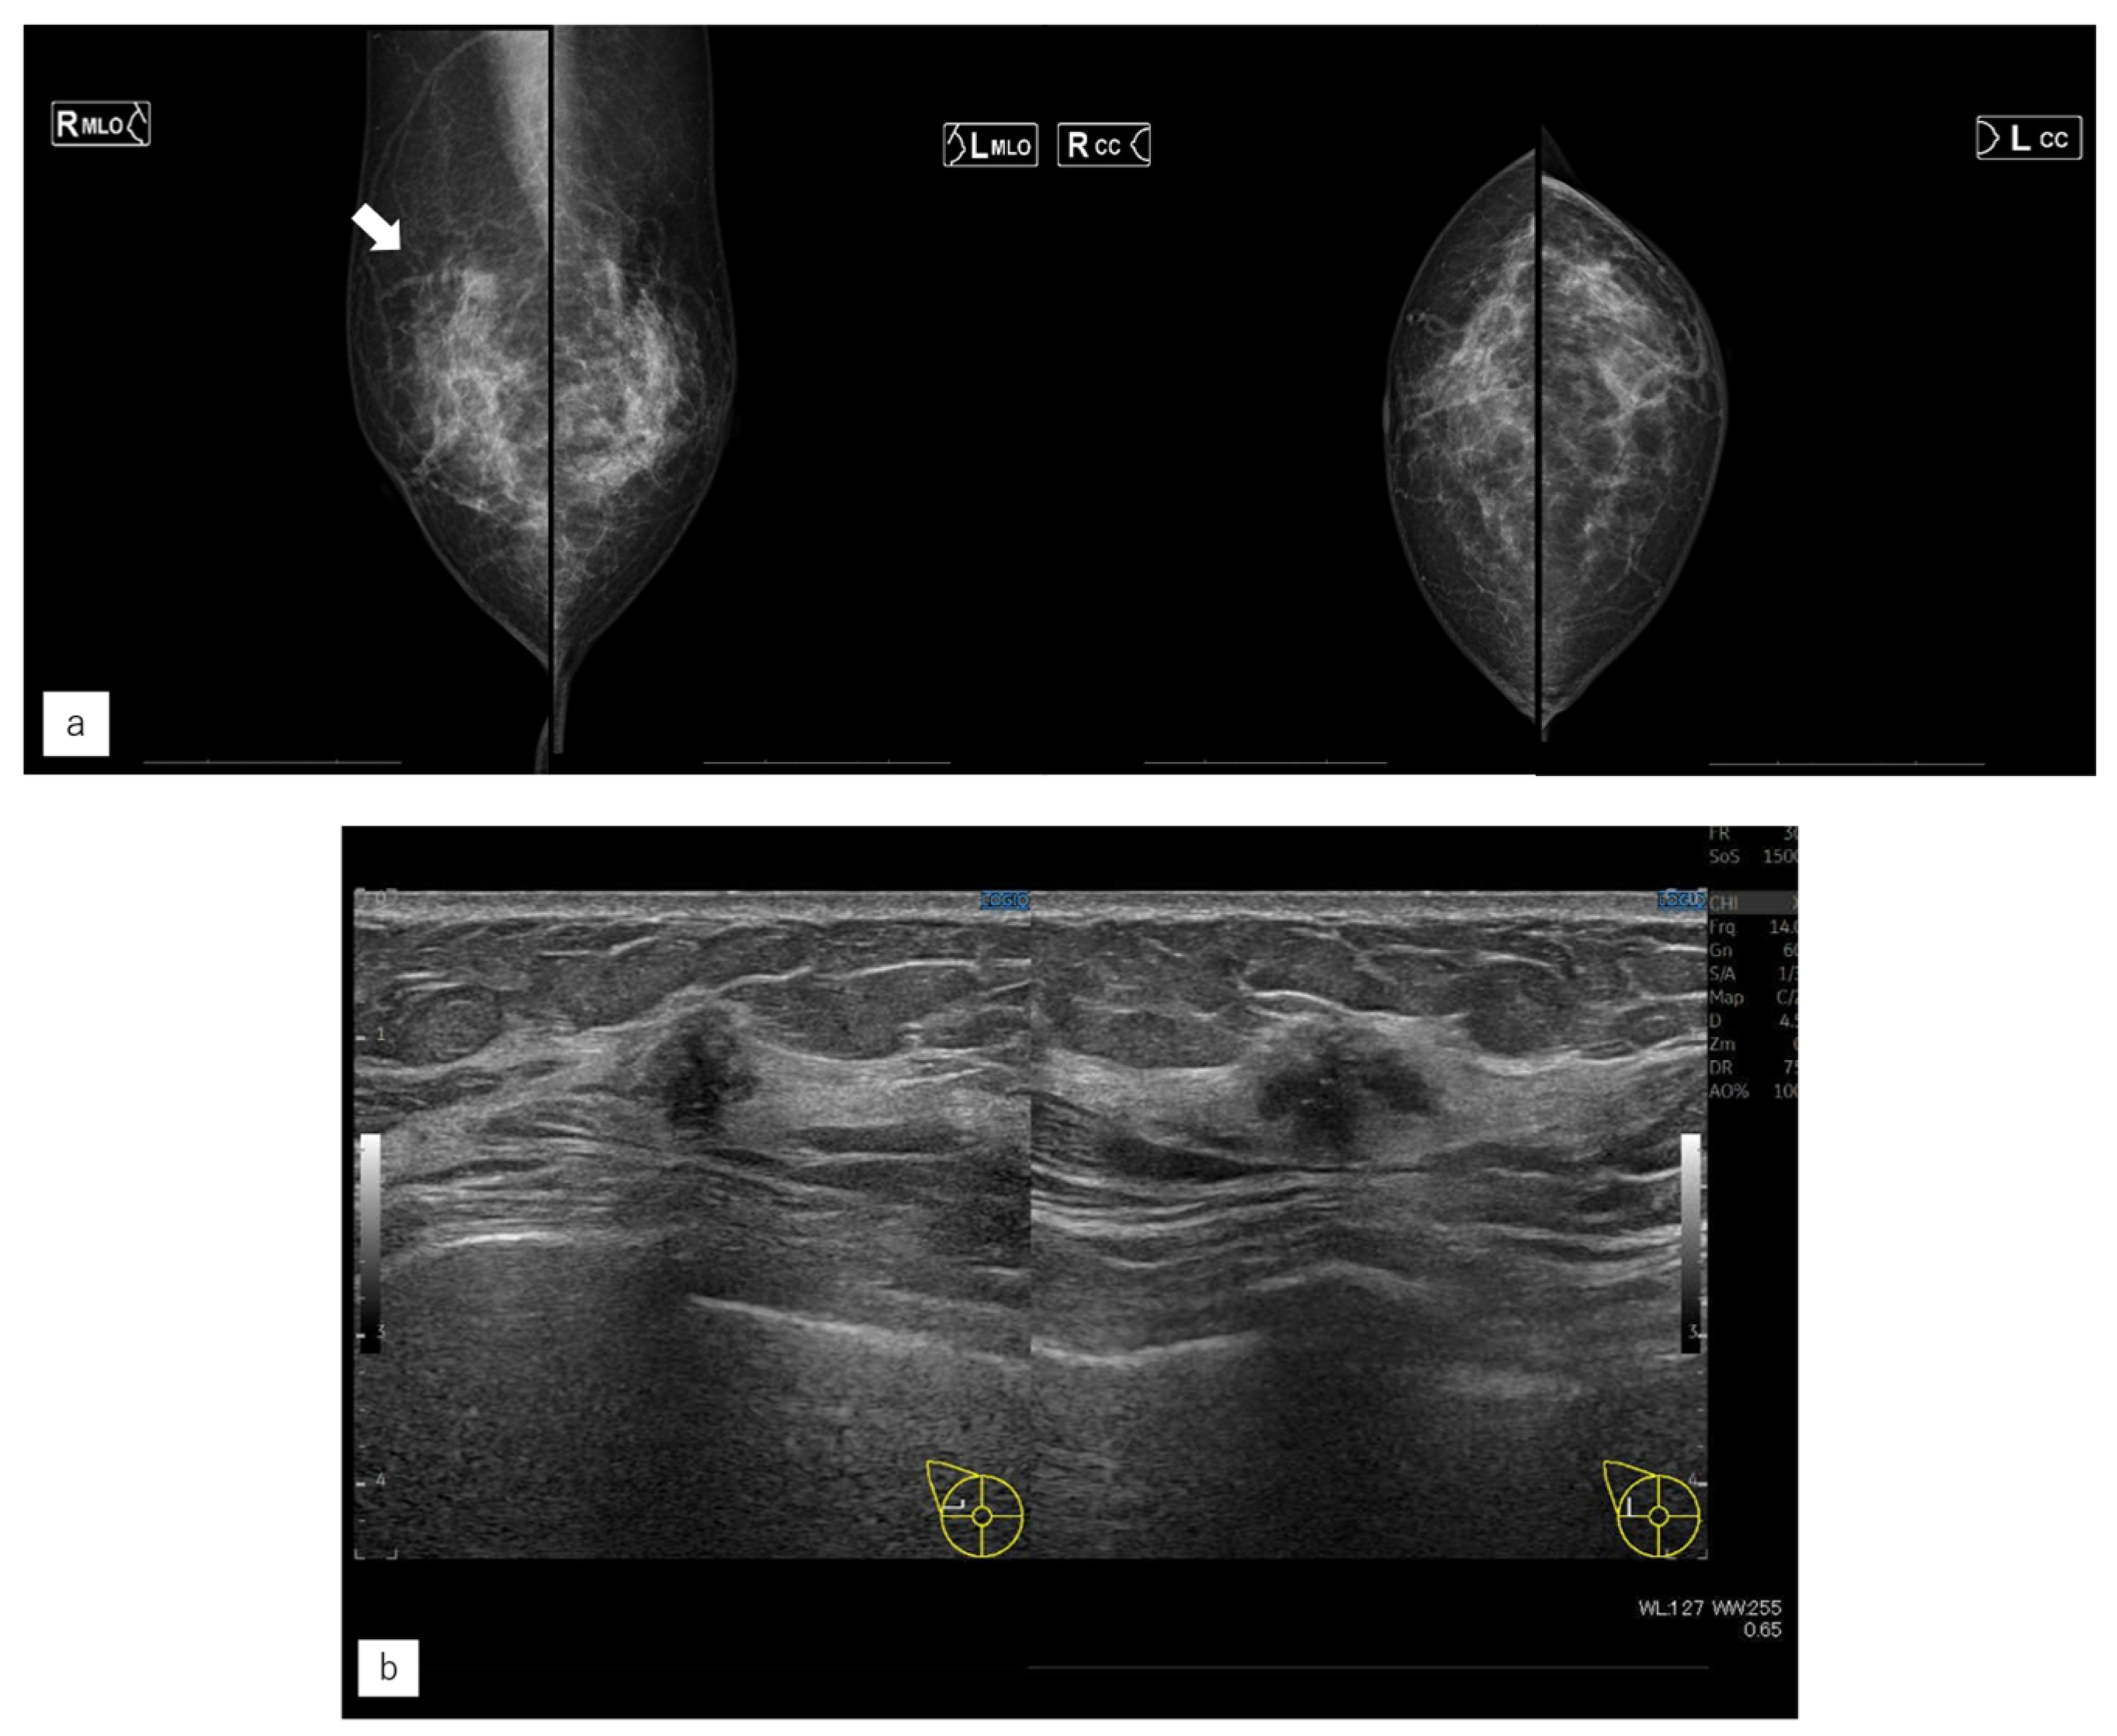

3.4. Representative Case